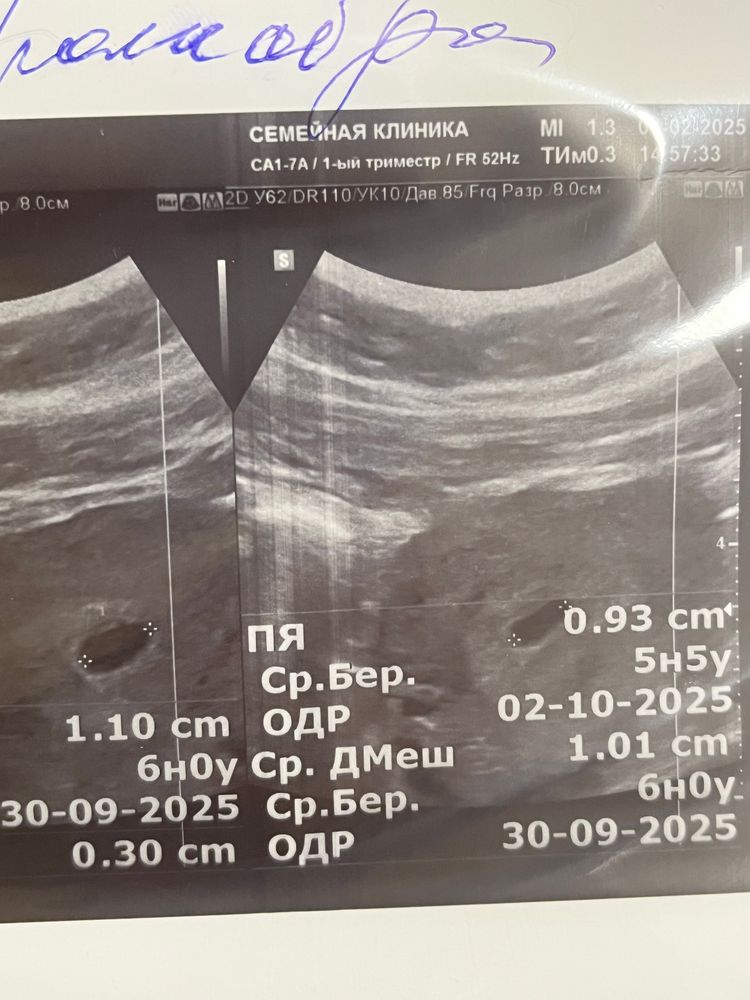

Кира, цикл 36-37 Я не понимаю как у узиста яйцо могло стать 6 недельное, желточный мешочек 5 недель 5 дней, если акушерский щас 6 недель 4 дня, а акушерский у нее вообще 7-8 недель Изображение Изображение

Вот сами фото узи, верхнее трансвагигальное, нижнее абдоминальное, трансвагинальное я сама уже выпросила, так как врачи гинекологи обычно его и делают на ранних сроках, красным видылила горошину которую мы изначально восприняли как эмбрион, потом она решила что это не плод а желтый мешочек так как сердце не слышно Изображение Изображение Изображение

Марии , вот пришло сегодня утром, не знаю не мало для эмбрионального 4 недели и 4 дня, а если по акушерским судить то еще меньше и даже не хватает для такого срока как по акушерским, по эмбриональному вроде достаточно но в приделах как вы думаете не мало ? Изображение